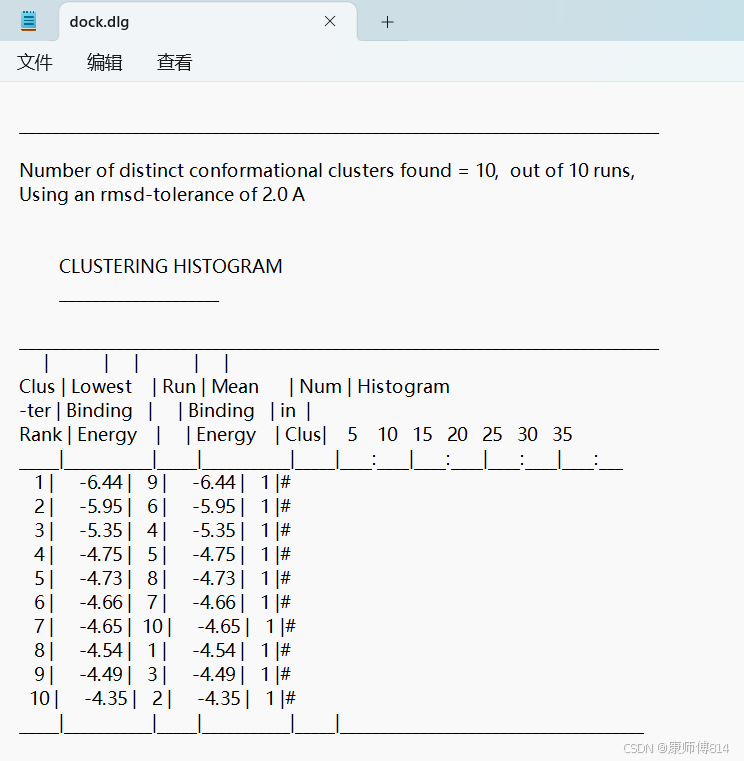

#另外,直接用记事本打开.dlg文件也可以直接看到所有对接结果的结合自由能